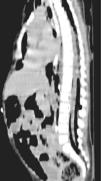

Figura 3.

Corte axial de TC a nivel lumbar en el que se aprecia la disposición del aire tanto anterior como posterior al saco dural.